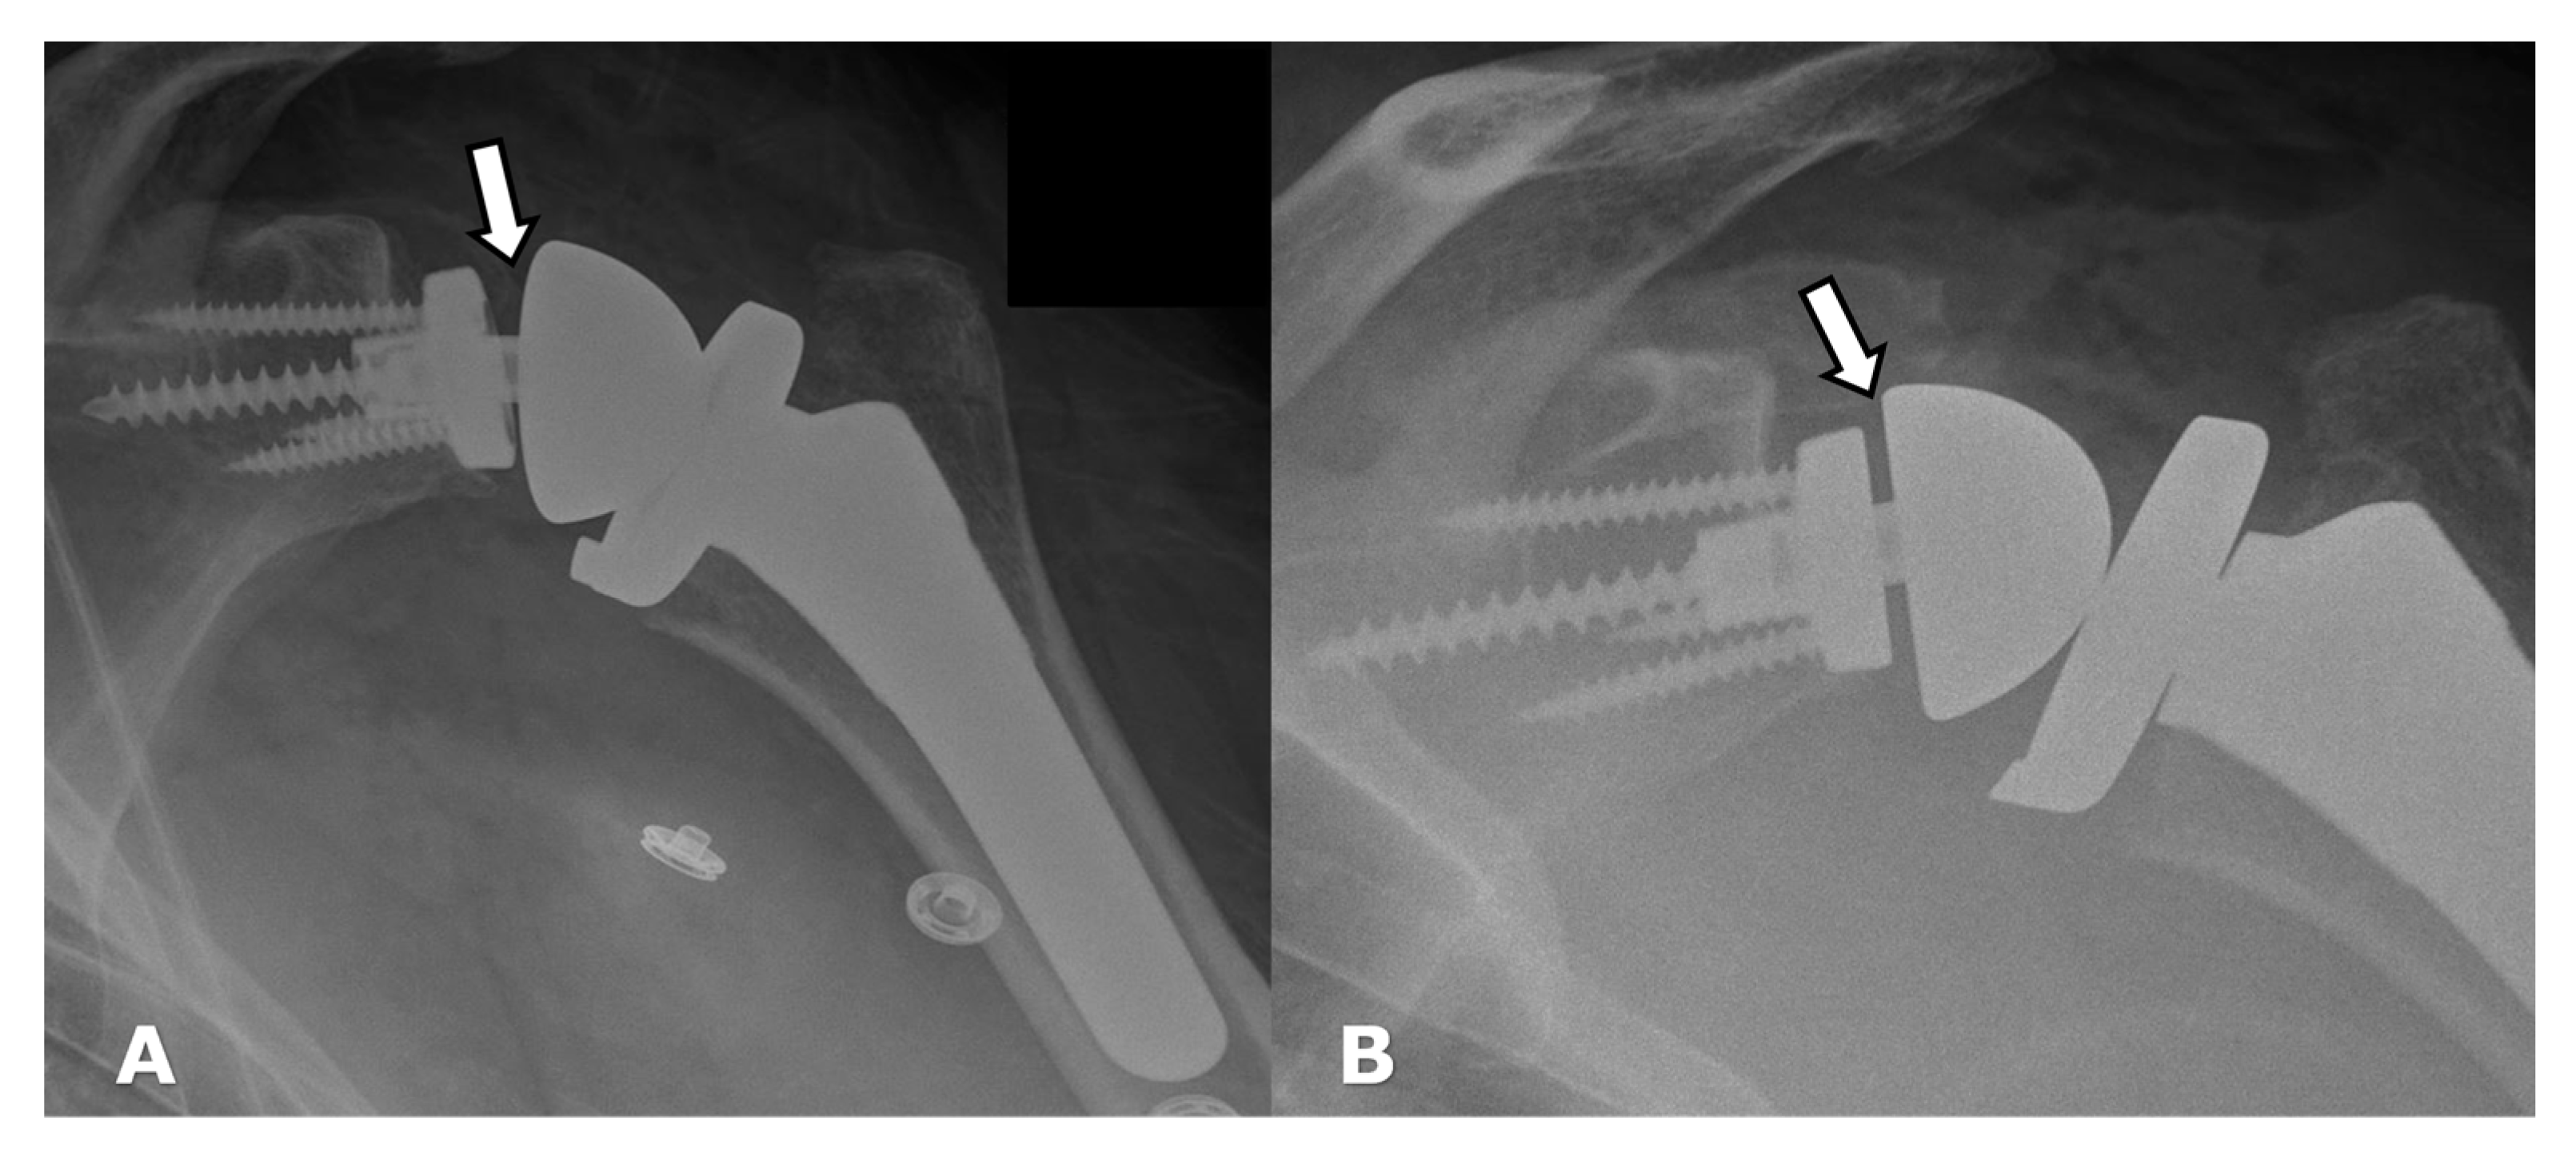

5.1.1. Humeral Head Resurfacing/Stemless Hemiarthroplasty (HHRA)

5.1.2. Hemiarthroplasty (HA)